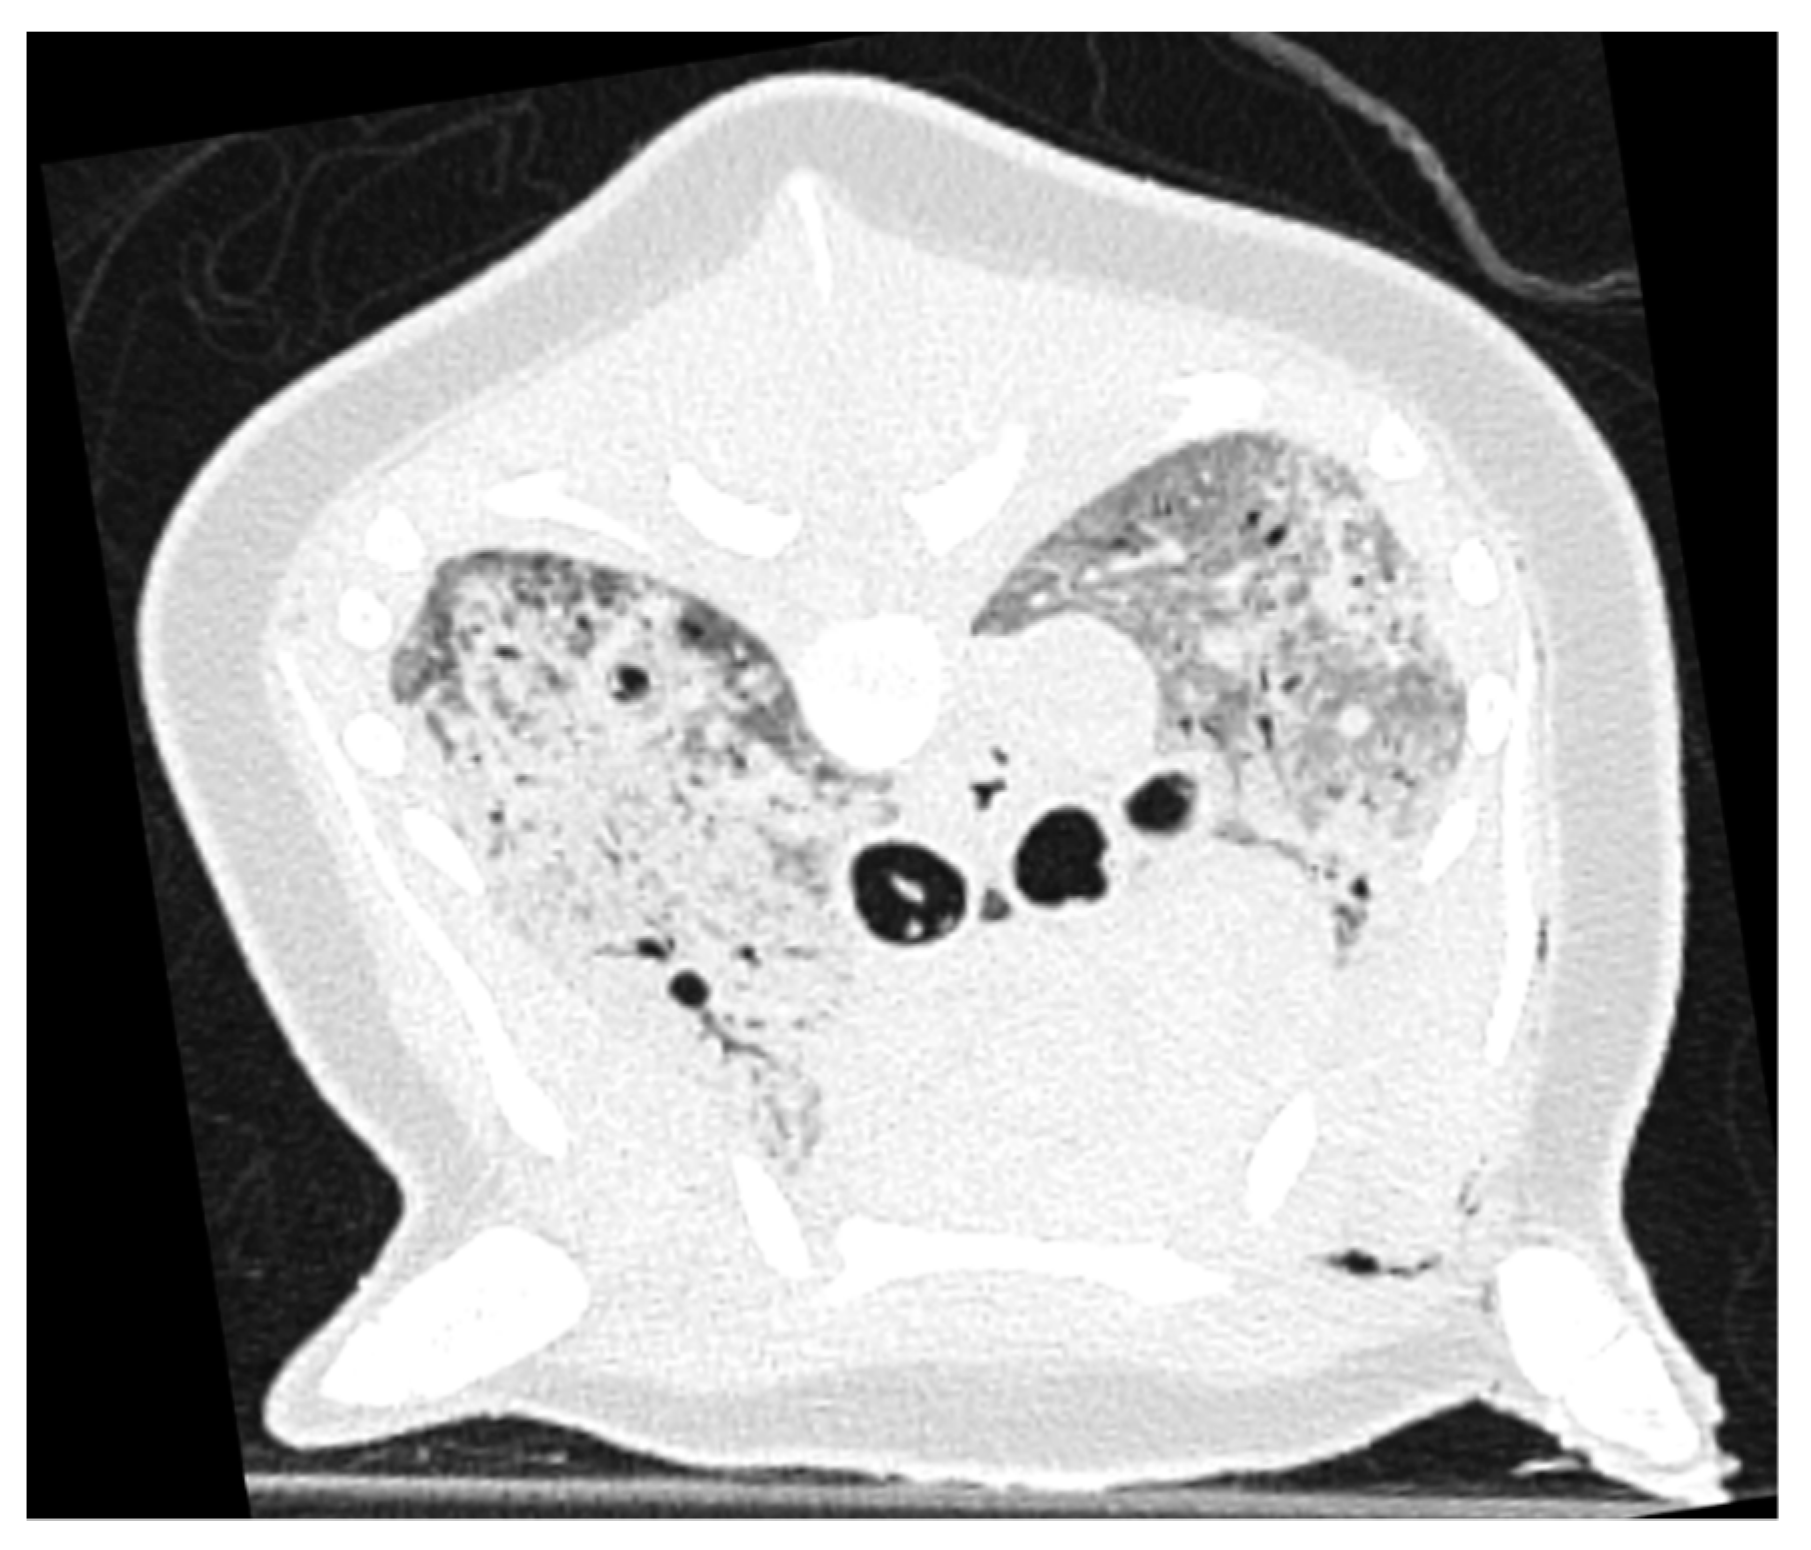

2.5. Pulmonary Parenchymal Attenuation Changes

3.4. Pulmonary Parenchymal Attenuation Changes